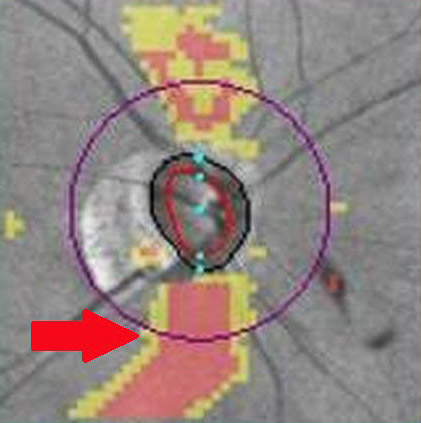

眼科詹立瑋醫師發現周小姐的視力、眼壓雖在正常值範圍內,不過視神經盤有凹陷變大、部分視神經萎縮,進一步安排光學同調斷層掃描,發現視網膜神經纖維變薄;而視野檢查,也明顯看到周小姐雙眼的視野出現狀況,上半部已經有一大塊的視野缺損,確診為青光眼,再不治療恐有失明之虞。詹立瑋醫師開立眼藥水,請周小姐按時點藥,經過三個月之後,她的兩眼眼壓降低,後續複診追蹤視神經纖維的厚度沒有再惡化變薄的情形,顯示青光眼趨於穩定。

左圖為經「光學同調斷層掃描」後顯示視網膜神經纖維缺損(箭頭處),有青光眼的病變;右圖為正常的視神經盤掃描圖。圖/台北慈院提供